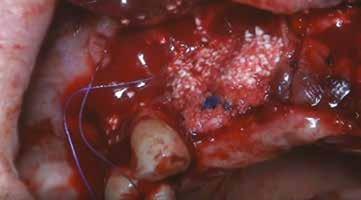

A progettazione implanto-protesica ultimata si disegna una dima chirugica che poi verrà stampata con Stampante 3D a tecnologia DLP. (fig. 07). L’intervento viene eseguito in anestesia locale con Articaina 1:200.000, si apre un lembo a tutto spessore e si posiziona la dima ad appoggio dentale, si inseriscono gli impianti programmati, si coprono alcune spire implantari esposte e si aumenta il volume osseo vestibolare con Sticky Bone. (fig. 08) A copertura della GBR si posiziona una membrana di CGF. Particolare attenzione viene posta nella sutura a più strati che ci dia contemporaneamente la certezza dell’immobilizzazione dell’innesto e della guarigione per prima intenzione della ferita. (fig. 09-10). Dopo circa 5 mesi si procede con la riapertura degli impianti (fig. 11) e dopo la guarigione dei tessuti si prende impronta ottica con Scan Bodies.

Raccolto il consenso del paziente si procede col programma iniziando con il Sinus Lift del quadrante 2 eseguito con accesso laterale e utilizzando biomateriale + CGF. (fig. 17-18-19-20-21-22)